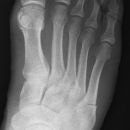

Lisfranc Luxationsfraktur